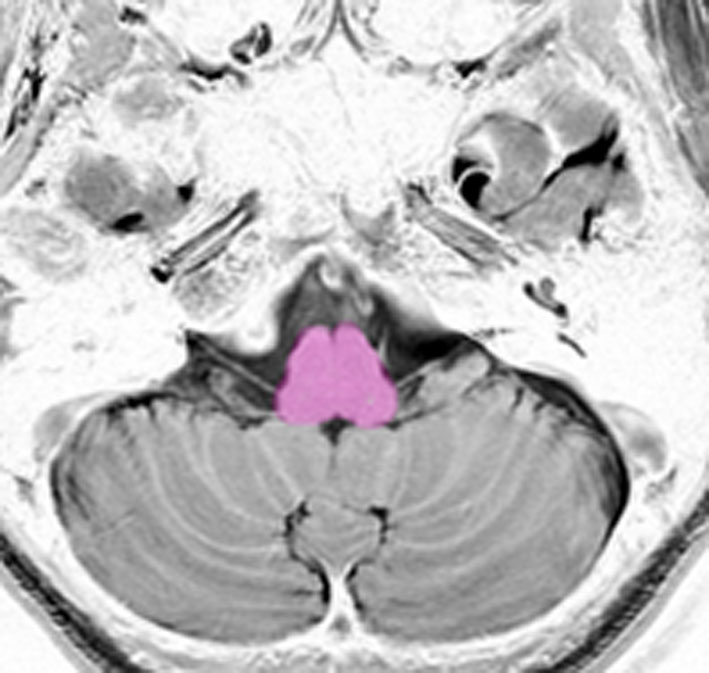

これは脳の中心部を縦切りにした写真です。脳幹部は上から順に,中脳 midbrain (黄色),橋 pons(オレンジ),延髄 medulla oblongata(ピンク)と呼ばれます。

意識の中枢。第3脳神経(動眼神経),第4脳神経(滑車神経)が出ます。

中脳の背側は,中脳視蓋(上丘と下丘)といって眼球運動や聴覚の中枢になっています。

中脳の中央に中脳水道という髄液の流れる管があります。その周囲の灰白質を,PAG periaqueductal gray matterといいます。刺激,ストレスや外傷に対する,抗侵害反応,行動制御(動機付け行動),自律神経反射,痛みの受容制御などをコントロールしています。